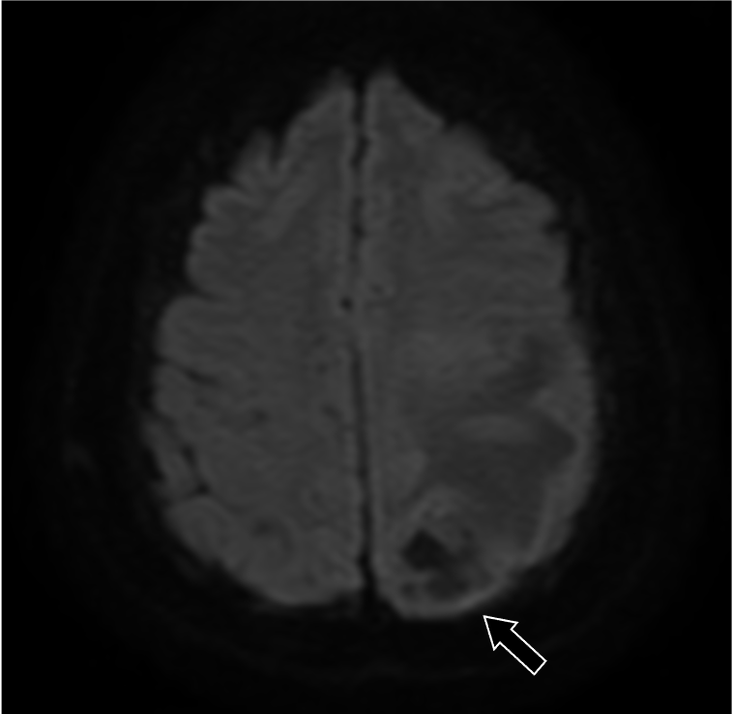

202X年より右手指知覚障害、頭痛を自覚。数日後から頻回嘔吐や右下肢運動障害があり、頭部造影MRIにて精査。既往に転移性肺腫瘤の治療歴あり。

症例解説

201X年腎細胞癌に対して手術を施行。術後経過で肺転移が出現。外科的切除および化学療法にて縮小を維持していた。202X年神経症状が出現し、頭部造影MRIにて左頭頂葉の孤発性脳転移と診断された。開頭腫瘍摘出術および定位照射を行い、再発なく経過している。

造影MRI検査は単純MRI検査と比較して、追加病変の検出能や診断精度の向上が示されている。造影MRI検査は、非腫瘍性白質疾患(慢性微小血管虚血性疾患など)を転移性腫瘍と鑑別する上でも有用である。脳腫瘍では腫瘍周囲に血管原性浮腫を認める場合があるが、高悪性度の原発性脳腫瘍と比較して、転移性脳腫瘍では腫瘍径に対する血管原性浮腫の面積が広いことが報告されている。単純MRI検査では腫瘍径を過大評価する可能性があり、術前・放射線治療計画等に際して造影MRI検査による適切な評価が求められる。